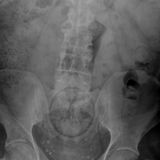

Die Webseite radiopaedia.org zeigt, welche Dinge Ärzte auf Röntgenbildern schon entdeckt haben. Die Aufnahmen wirken skurril und erschreckend zugleich und machen deutlich, wie weit die eingeführten Dinge bereits in den mescnhlichen Darm vordringen können.

Aber Glück im Unglück für die Patienten: Die Gegenstände können meist ohne Operation entfernt werden. Sehen Sie hier einige der spektakulärsten Röntgenaufnahmen. Da runzeln selbst Chirurgen die Stirn.